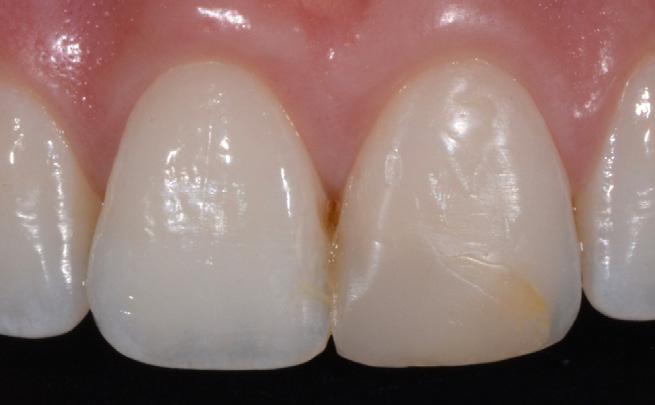

Images courtesy of Dr A. Mak, Australia Images courtesy of Dr Y. Choi, Australia

Invisible aesthetics even for extreme challenges

In addition to its 5 core shades G-ænial A’CHORD extends its portfolio with 2 cervical shades for elderly patients, 3 opaque for masking discolouration, 2 enamel for life-like translucency and 2 bleach shades for brighter smiles, thus making it possible to create invisible fillings even for extreme challenges.

G-ænial A’CHORD Images courtesy of J. Tapia Guadix, Spain Images courtesy of Dr W. Boujemaa, France Images courtesy of Dr G. Benjamin, Germany G-ænial A’CHORD veneer on tooth 11 Near-UV 405 nm initial situation Conventional composite veneer on tooth 11